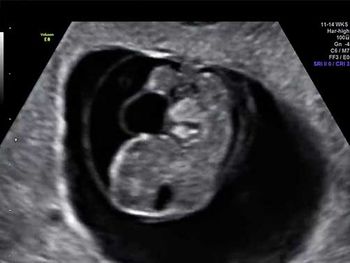

Challenge your diagnostic skills with this image of a fetal head.